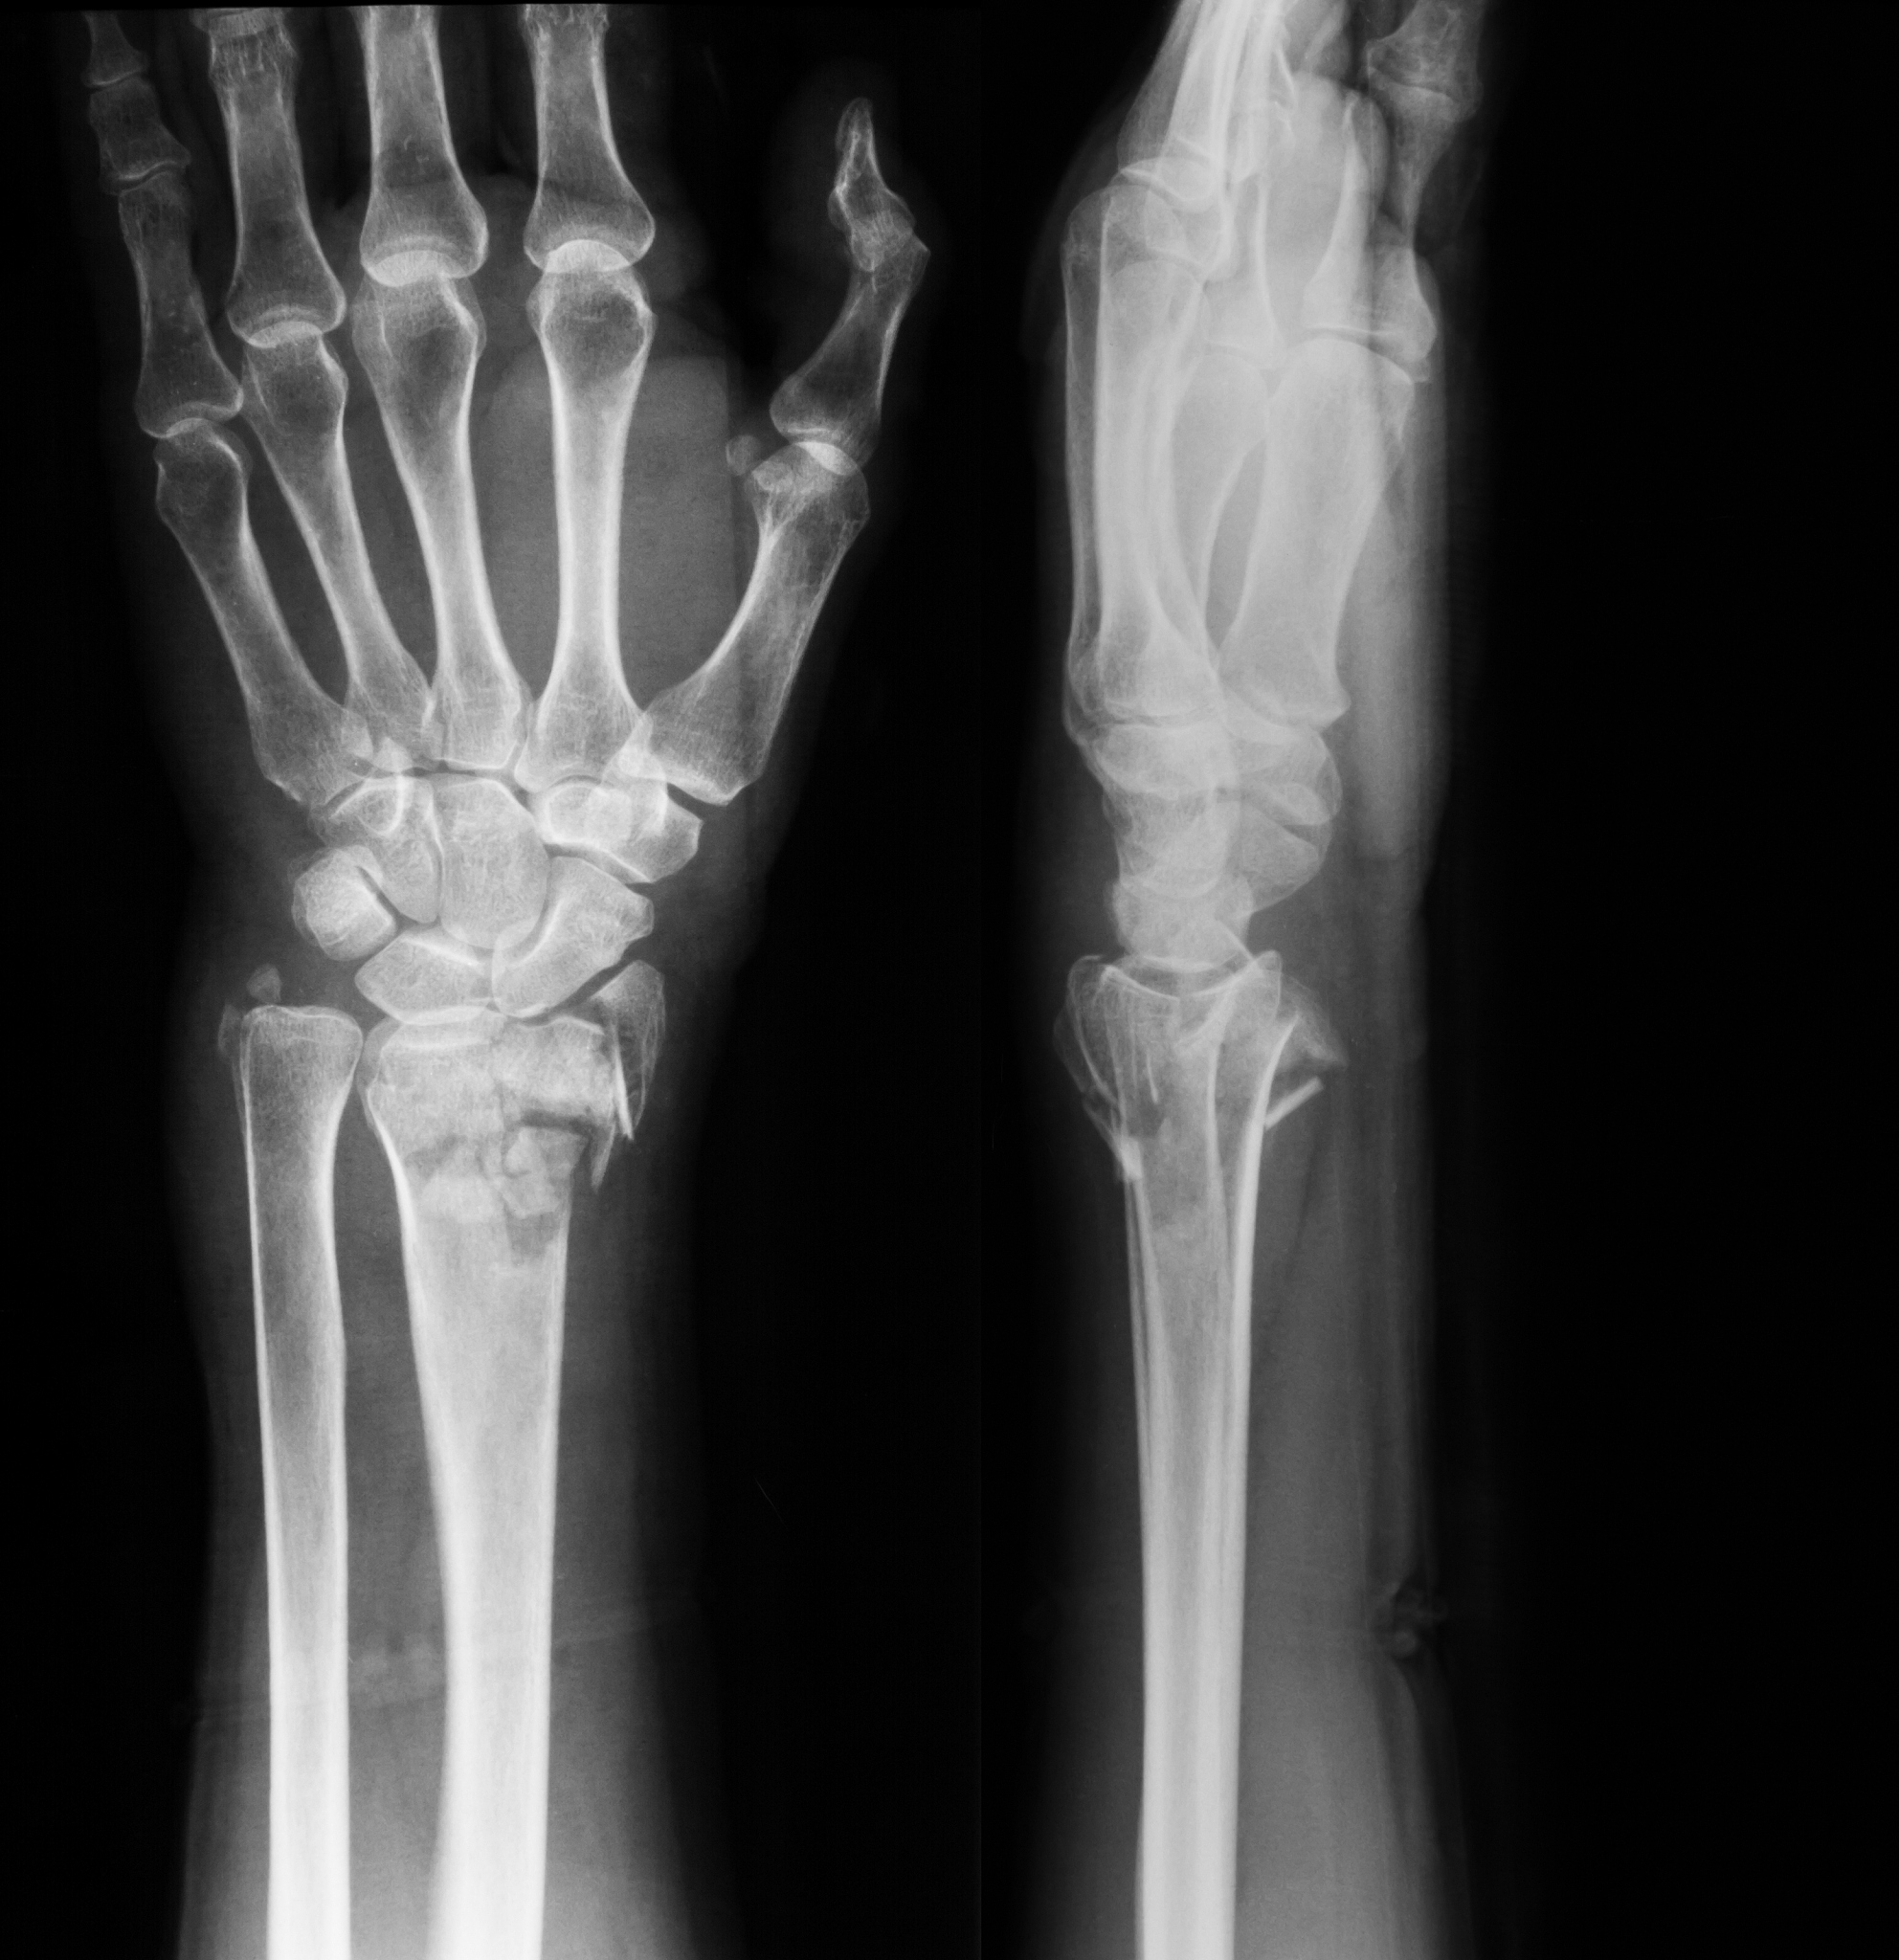

患者女66岁因春季疫情居家隔离满2周后外出采购日用品时摔倒髋部疼痛不能站起右手腕部疼痛、变形。经检查发现股骨颈和桡骨远端均骨折。请从解剖学角度分析该患者为什么容易发生骨折?